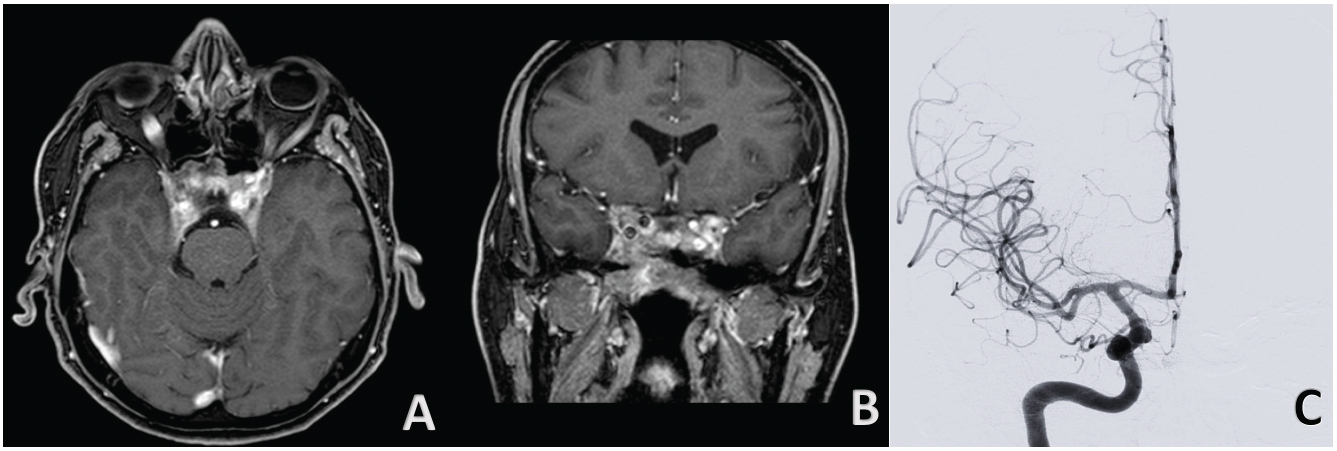

Non-contrast head CT revealed a large destructive central skull base mass with hyperdensity in his context. A further examination with pre-and post-gadolinium brain MRI, underlined the limits of the skull base mass centred in cellar region with erosion of sphenoid sinus and clivus. It was extended inferiorly to the magnum foramen and occipital condyles, laterally to the petrous apices, sigmoid sinus and jugular bulbs; superiorly occupying the chiasmatic cistern, encasing optic nerves and both internal carotid arteries (Figure 1). A large flow void, within the region of the right carotid siphon has been shown (Figure 2). Digital subtraction angiography (DSA) was performed that confirmed a pseudo-aneurysm of cavernous segment of right ICA with a bleb on the anterior side (Figure 1).

Figure 1: Contrast-enhanced T1-weighted magnetic resonance images in the axial A) Coronal; B) And sagittal planes; C) Demonstrate an intra and parasellar tumor; Four-vessels angiogram in anteroposterior; D) And three-dimensional lateral view; E) Reveals a large pseudo-aneurysm of cavernous segment of right ICA with bleb on anterior side. View Figure 1

Post-gadolinium MRI 6 months after starting medical treatment (Figure 3) showed significant tumor shrinkage with decompression of the optic apparatus. Furthermore DSA (Figure 3) demonstrated almost complete resolution of aneurysm. Patient continued to be in good health during follow-up, with no bleeding or other complications.

Figure 3: Contrast-enhanced T1-weighted magnetic resonance images in the axial A) And coronal; B) After treatment demonstrate considerable reduction of prolactinoma size; Four-vessels angiogram in anteroposterior view; C) Reveals almost complete recovery of pseudoaneurysm. View Figure 3